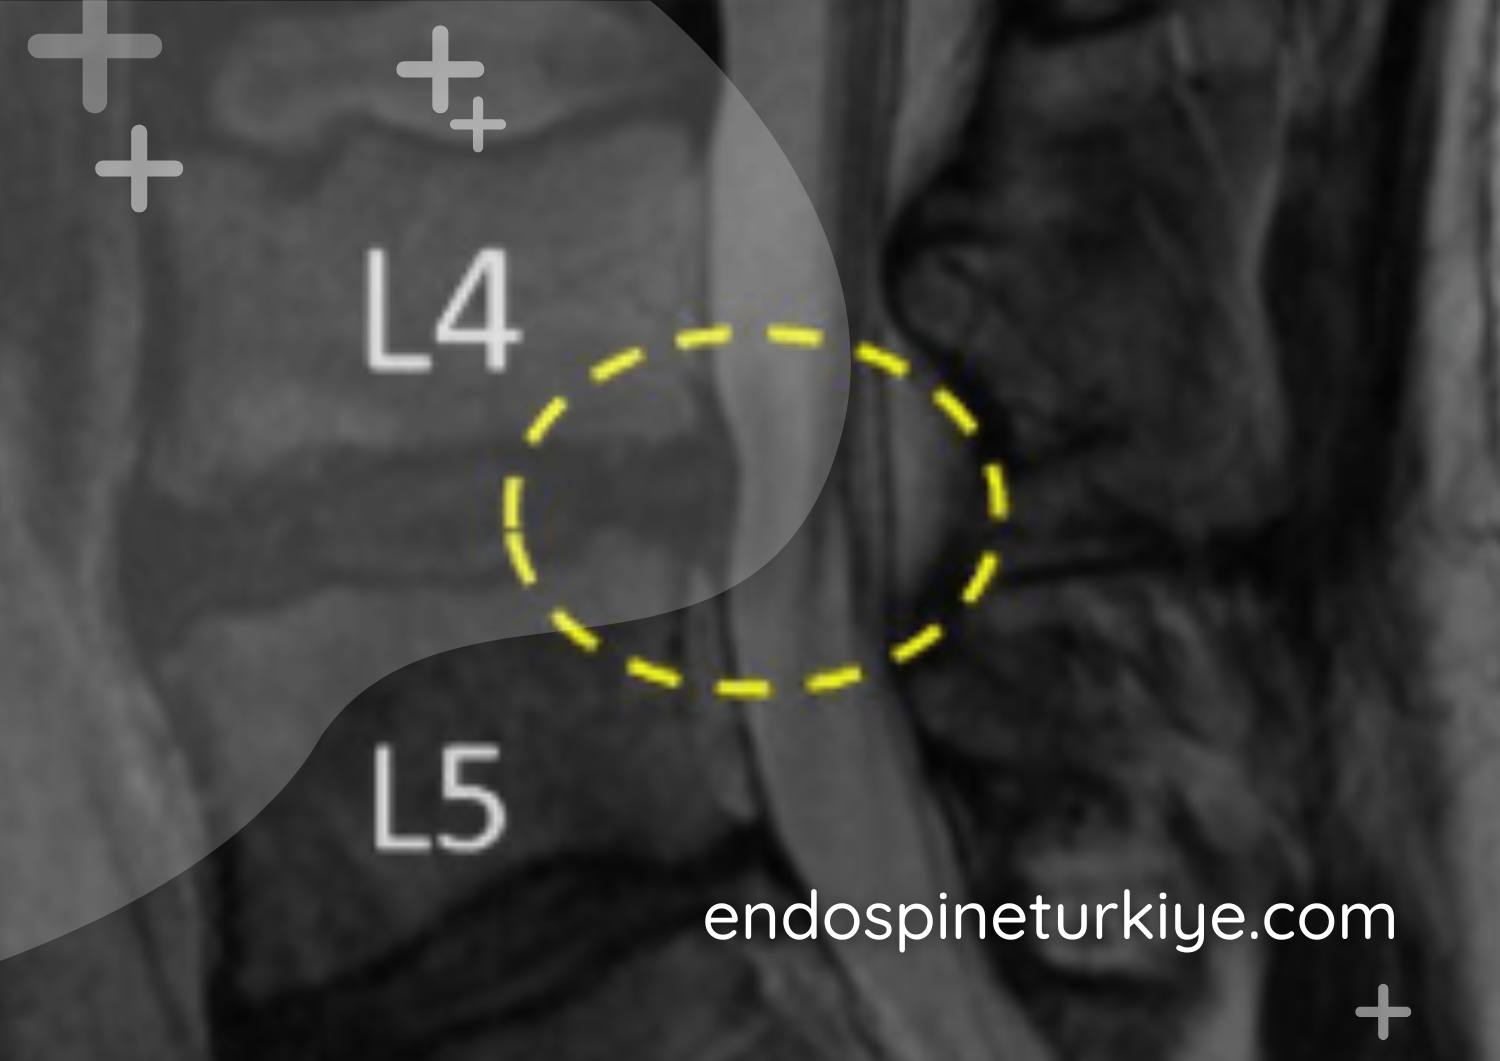

Kanal daralması ameliyatı sonrası - Genişletilmiş omurga kanalı

Tedavi Sonrası

Genişletilmiş kanal